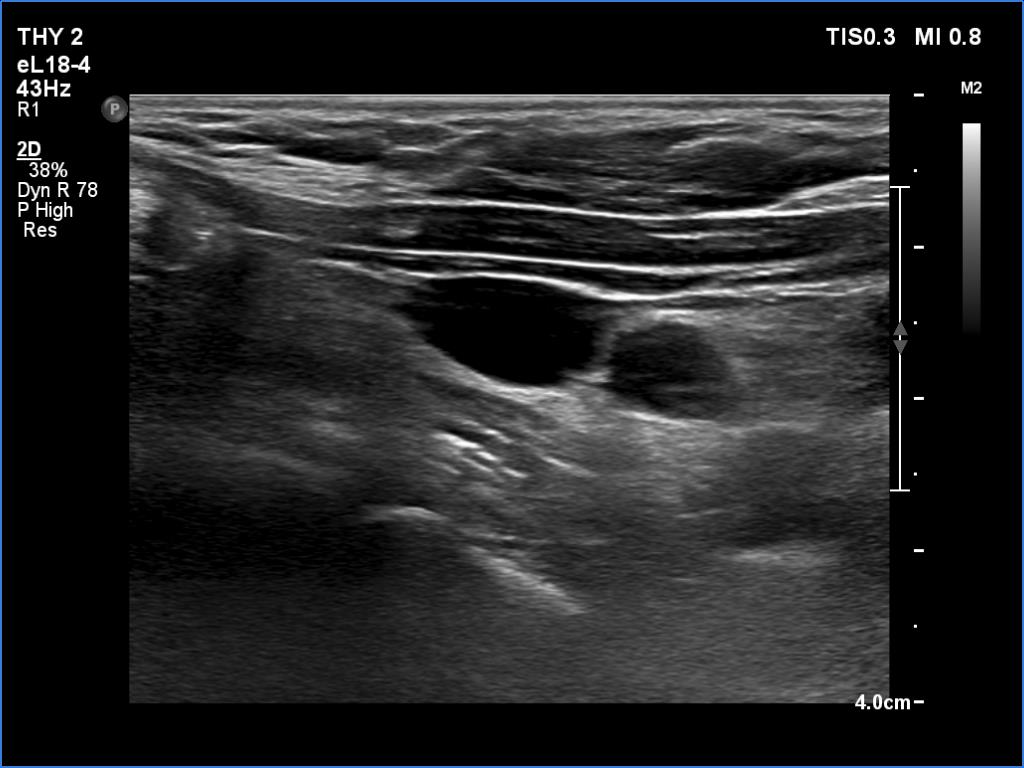

Second examination two years later (third row of images)

Clinical data: The patient had no complaints, she was on the 7th gestational week and came to follow-up.

Hormonal investigation TSH-level 4.17 mIU/L, on daily 125 microgram levothyroxine, thyroglobulin below 0.2 ng/mL, anti-hTg below 0.9 U/mL.

Ultrasonography was unchanged. Connective tissue was found in the upper part of the left thyroid bed while there was a cystic lesion in the lower half. On the location, the lesion corresponded to a parathyroid cyst. The dimensions of the cyst were 8x6x13 mm, width, depth and length, respectively.Suggestion: to increase the dose of the levothyroxine to daily 150 micrograms. TSH in 6 weeks.

Comment. On the location of the cystic lesion, this is probably of parathroid origin. Based on the stably undetectable thyroglobulin level, we have no reason to suggest that this would have oncological importance.